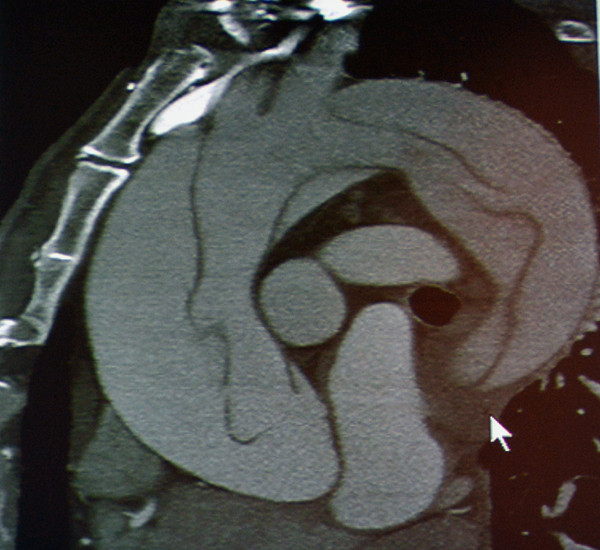

急性主动脉综合征:包括主动脉夹层、壁间血肿、穿透性溃疡。TRO可发现主动脉夹层的真假腔和内膜片。

图8 主动脉夹层Stanford A

图9 主动脉夹层Stanford B